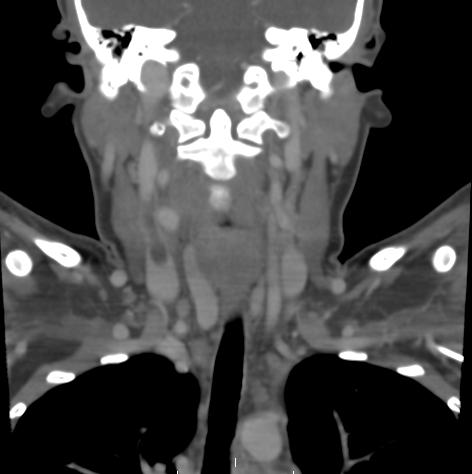

Lemierre’s Syndrome

Internal jugular vein thrombosis may be a complication of a pharyngeal infection. Extension of the infection to the jugular vein may be secondary to a para-pharyngeal abscess. If the thrombosis extends and embolizes this may result in septic thrombo-emboli to the lungs. This is called Lemierre’s syndrome. Lemierre’s syndrome may result in mortality.

The treatment of Lemierre’s syndrome is first and foremost antibiotics. There is uncertainty concerning the need for anticoagulation in these patients. However, most would probably treat these patients for a finite period of time, especially if clots do not resolve with antibiotics alone.